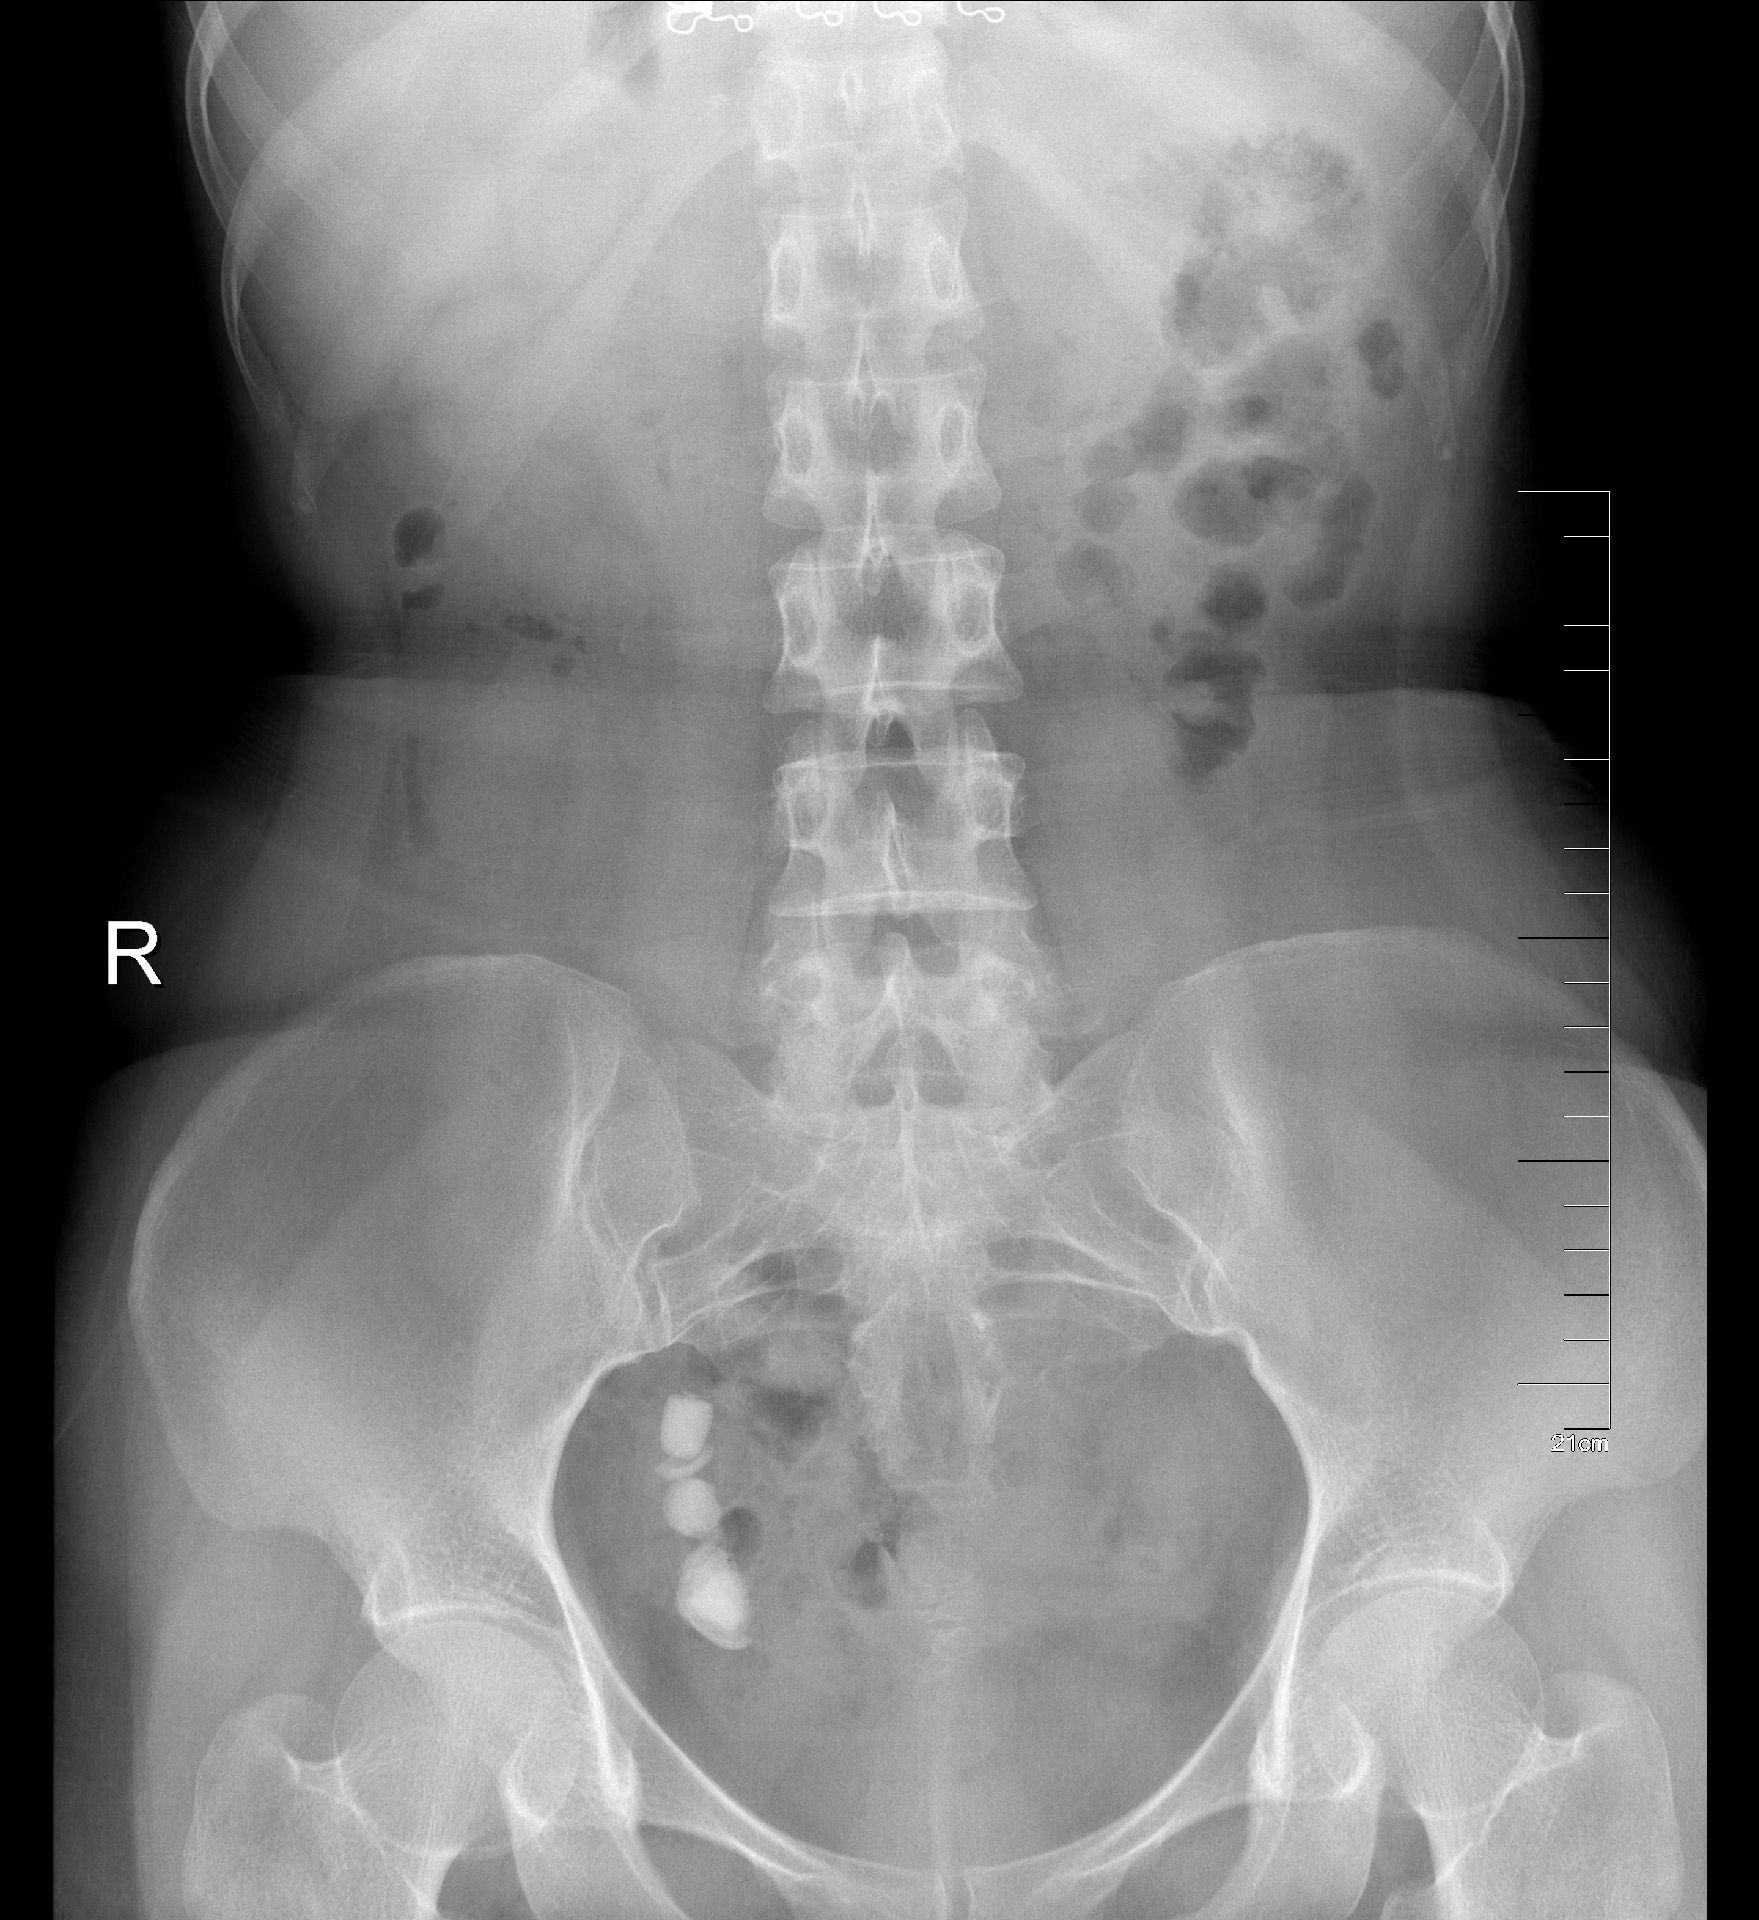

术后KUB见双肾造瘘管,及双侧内支架管固定妥善

正常人输尿管长约25cm左右,该患者输尿管迂曲扩张,长达35-40cm左右,裁剪部分输尿管成型